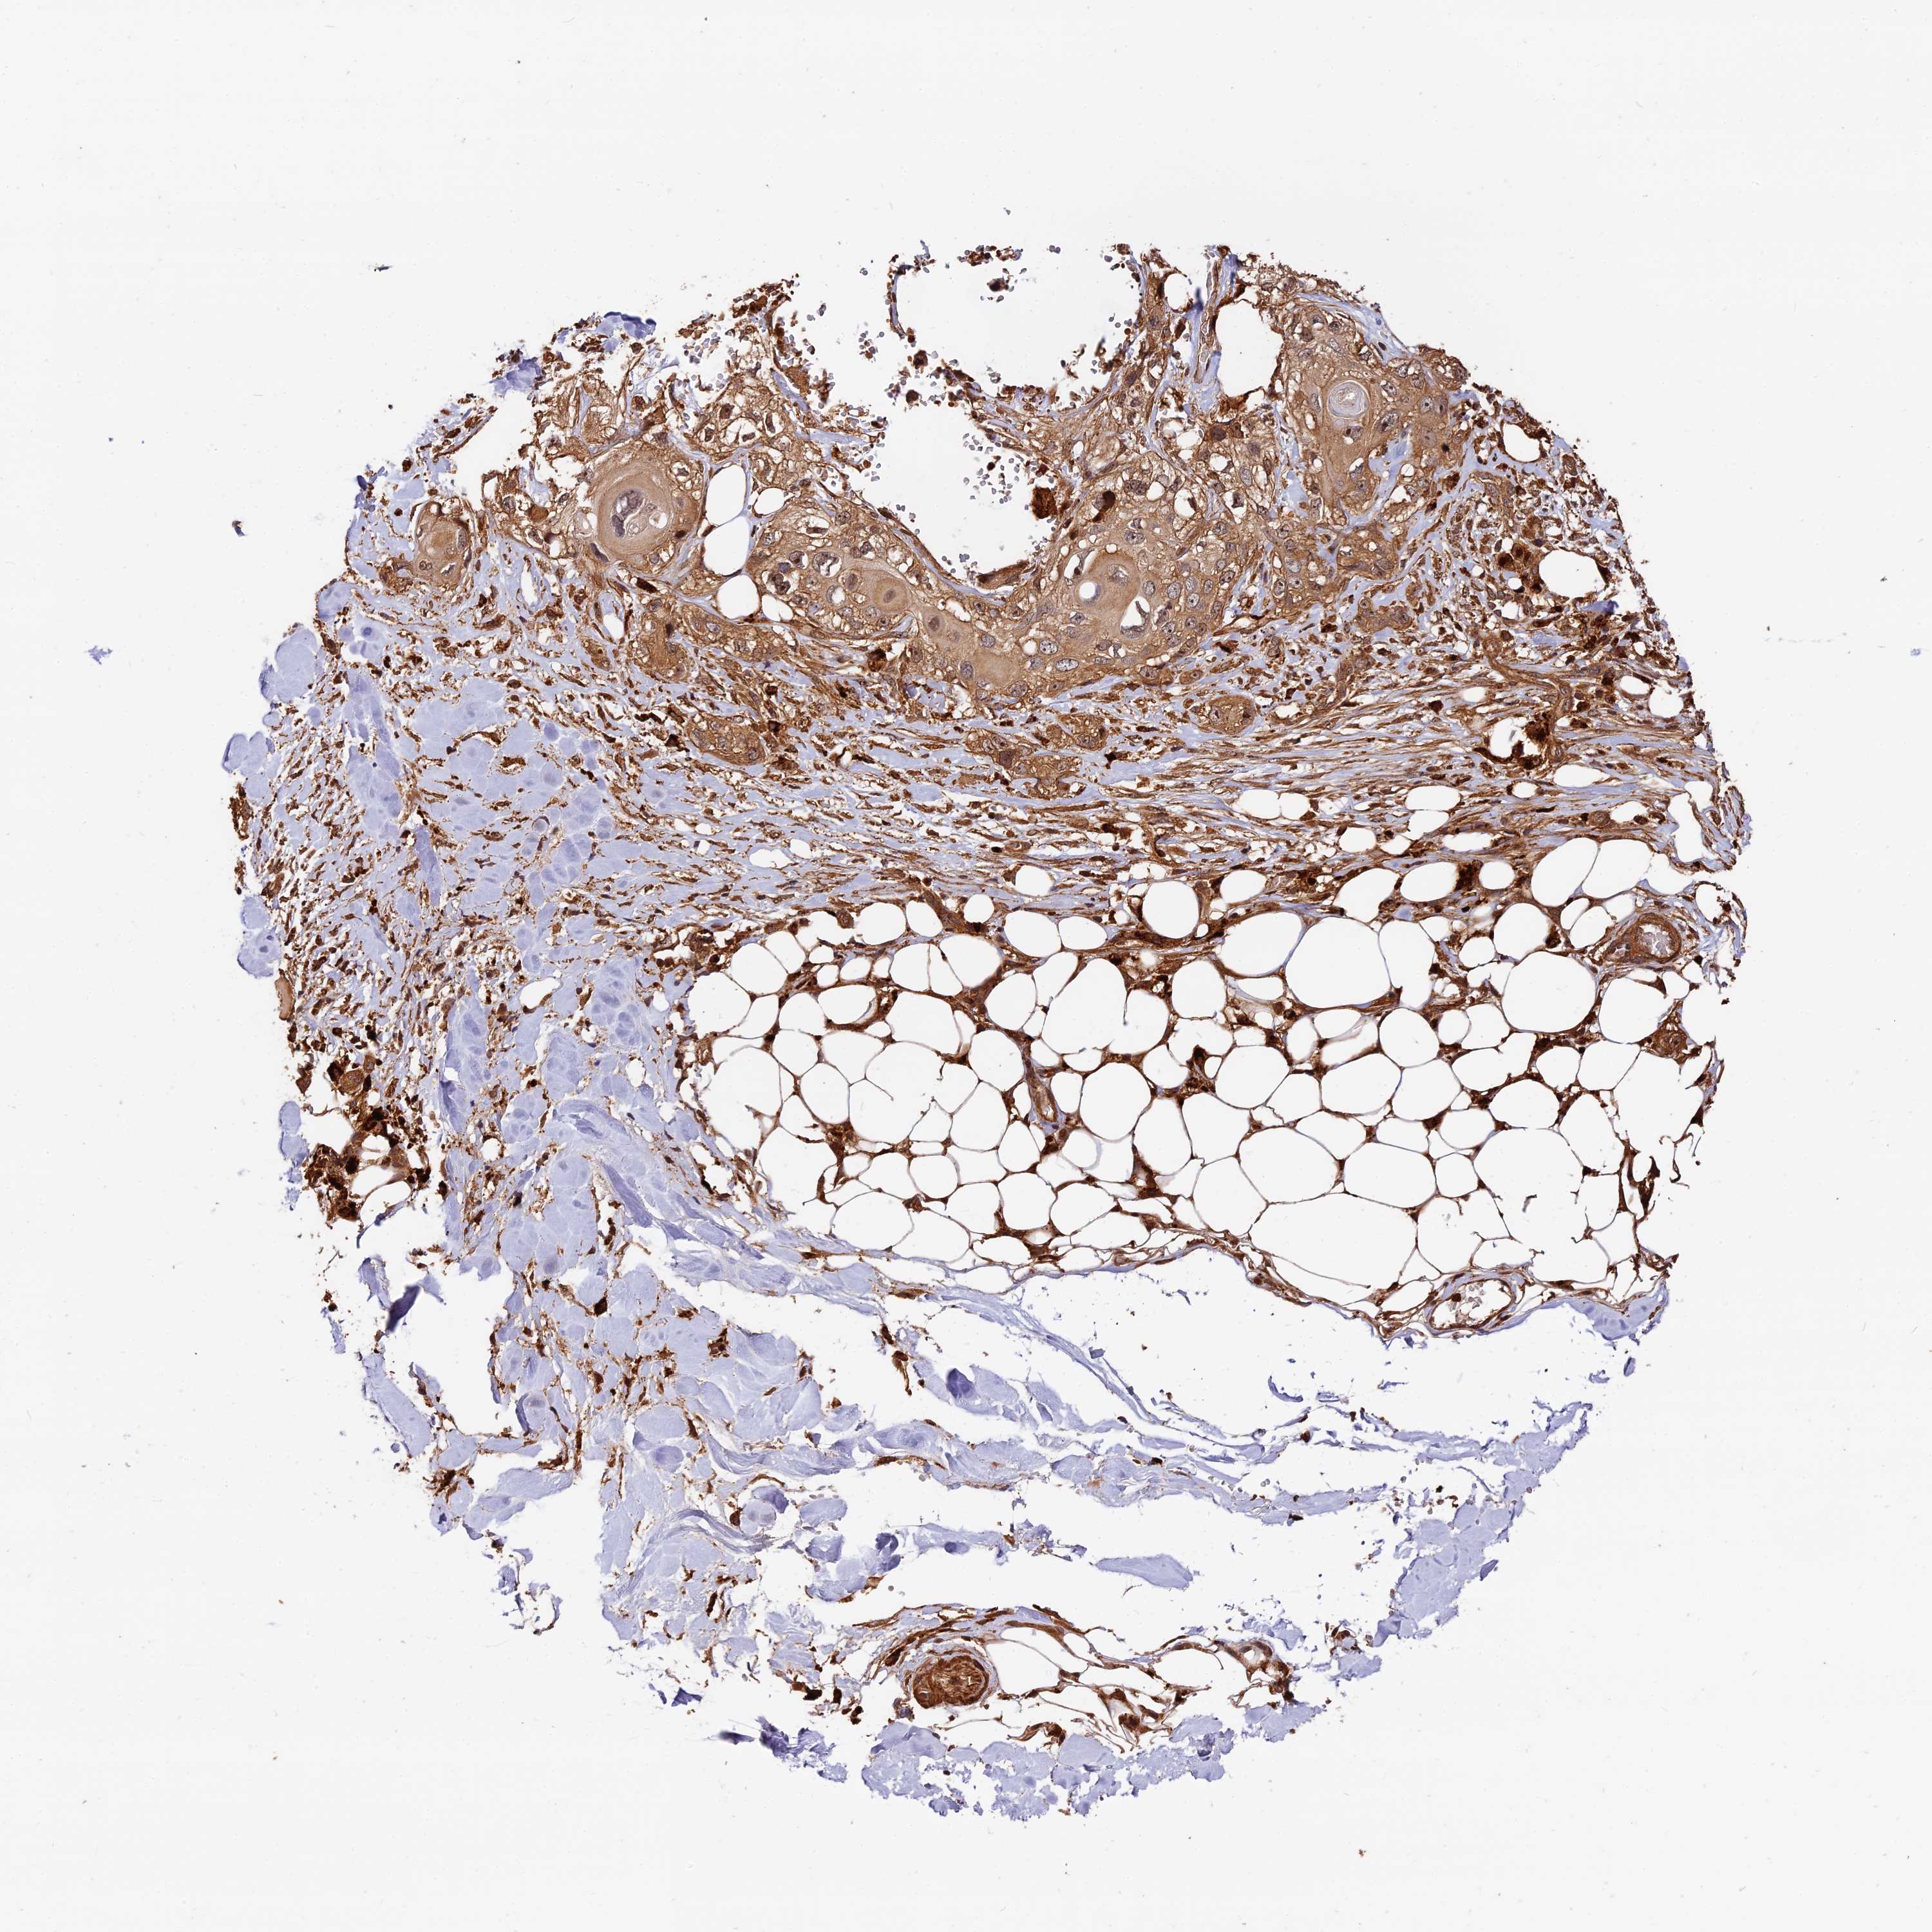

Basal cell and squamous cell cancer

SKIN CANCER - Protein expressioni

A mouse-over function shows sample information and annotation data. Click on an image to view it in a full screen mode. Samples can be filtered based on level of antibody staining by selecting one or several of the following categories: high, medium, low and not detected. The assay and annotation is described here.

Antibody stainingi

Antibody staining in the annotated cell types in the current human tissue is reported as not detected, low, medium, or high, based on conventional immunohistochemistry profiling in selected tissues. This score is based on the combination of the staining intensity and fraction of stained cells.

Each image is clickable and will lead to virtual microscopy that enables deeper exploration of all samples and also displays staining intensity scores, fraction scores and subcellular localization as well as patient and tissue information for each sample.

Antibody HPA040390

Antibody CAB002611

Squamous cell carcinoma, metastatic, NOS